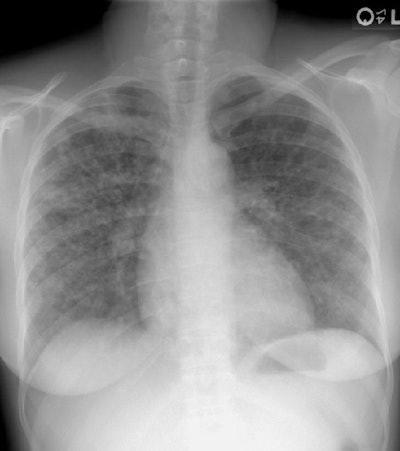

Sarcoid- Stage 3

The patient was an active duty troop who presented with complaints of increasing shortness of breath during physical fitness training. The patient stated that they had been previously diagnosed with sarcoid. Their chest radiograph demonstrated a diffuse reticulonodular appearance to the lungs (which was confluent in areas- particularly the right upper lung) and no evidence of hilar or mediastinal adenopathy. The findings were consistent with stage 3 sarcoid. Very likely the patient had progressed from earlier stages, but those films were not available.